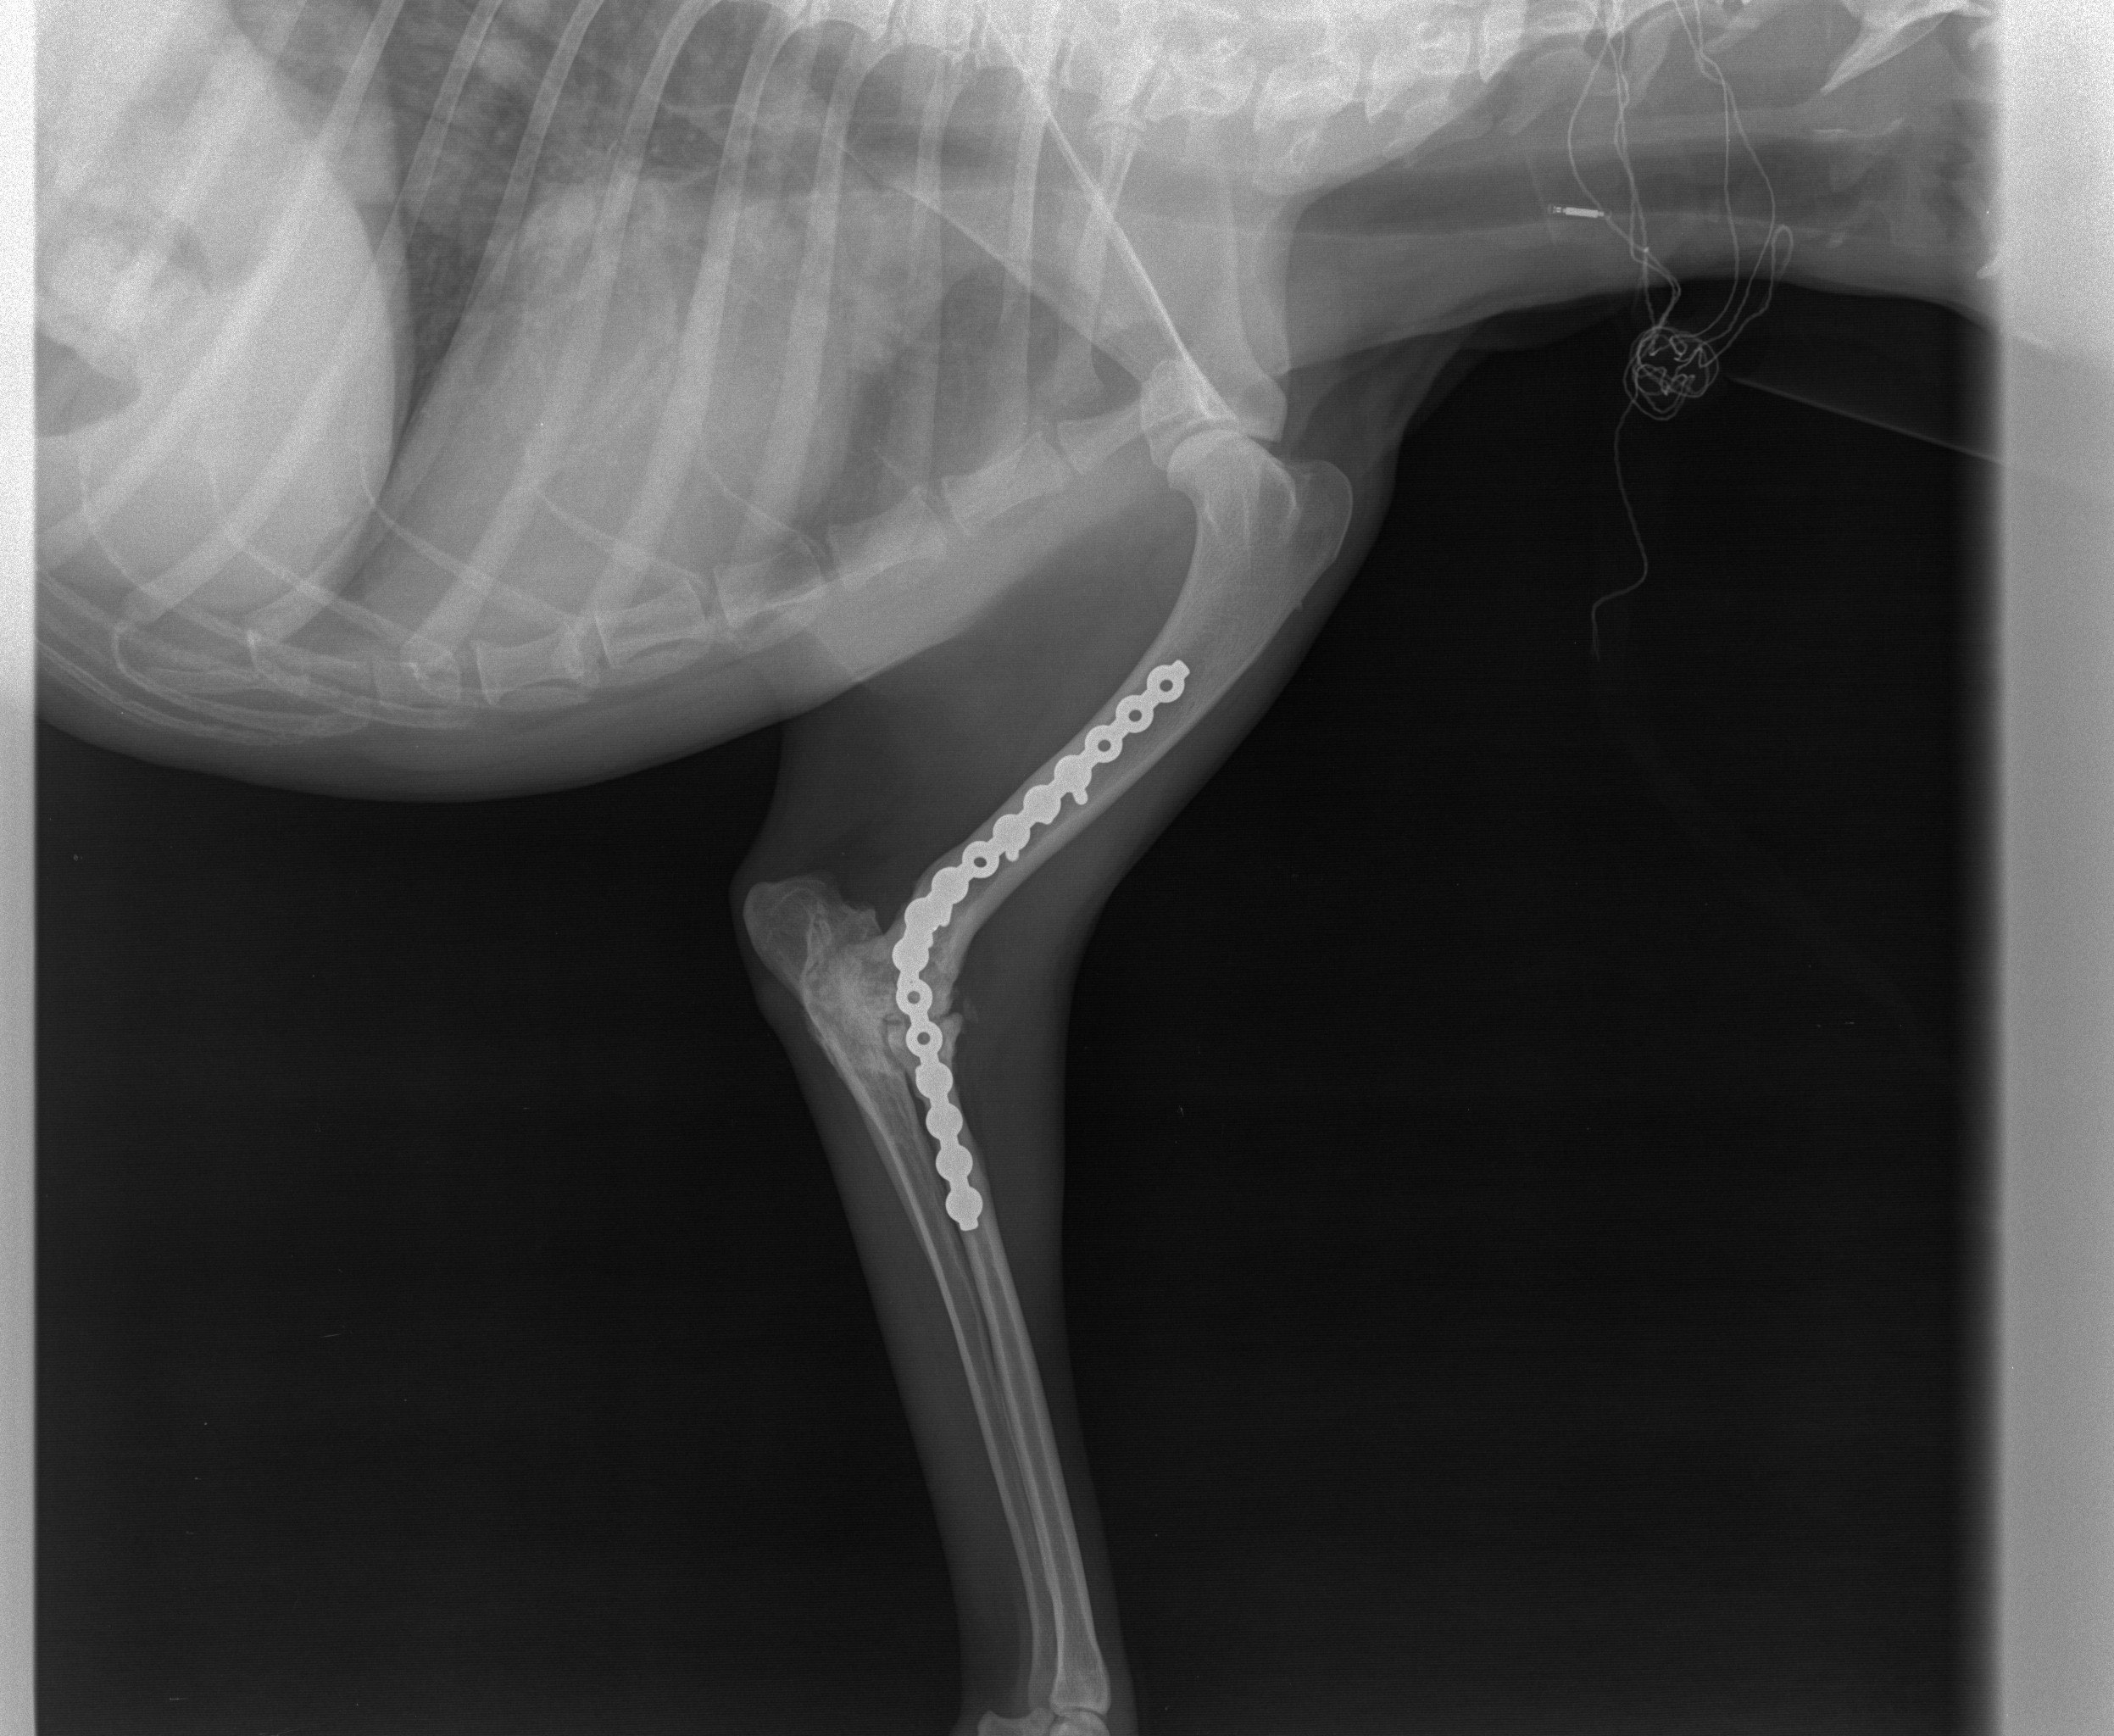

Der schmusige, anhängliche ca 6jährige Velitschko kam in die Schweiz mit einer Platte im Bein und hinkend. Eine Kontrolle beim Chirurgen ergab, die Platte wird drin bleiben müssen, er belastet sein Bein jedoch falsch, was durch Physiotherapie sicher massiv verbessert werden kann. Also hat sich Lilo bereit erklärt, ihn jeweils zur Physio zu DogVita in Bichelsee zu fahren. Das wird sicher eine längere Geschichte, hat aber gute Erfolgsaussichten! Wer hilft mit, die entsprechenden Kosten zu tragen?